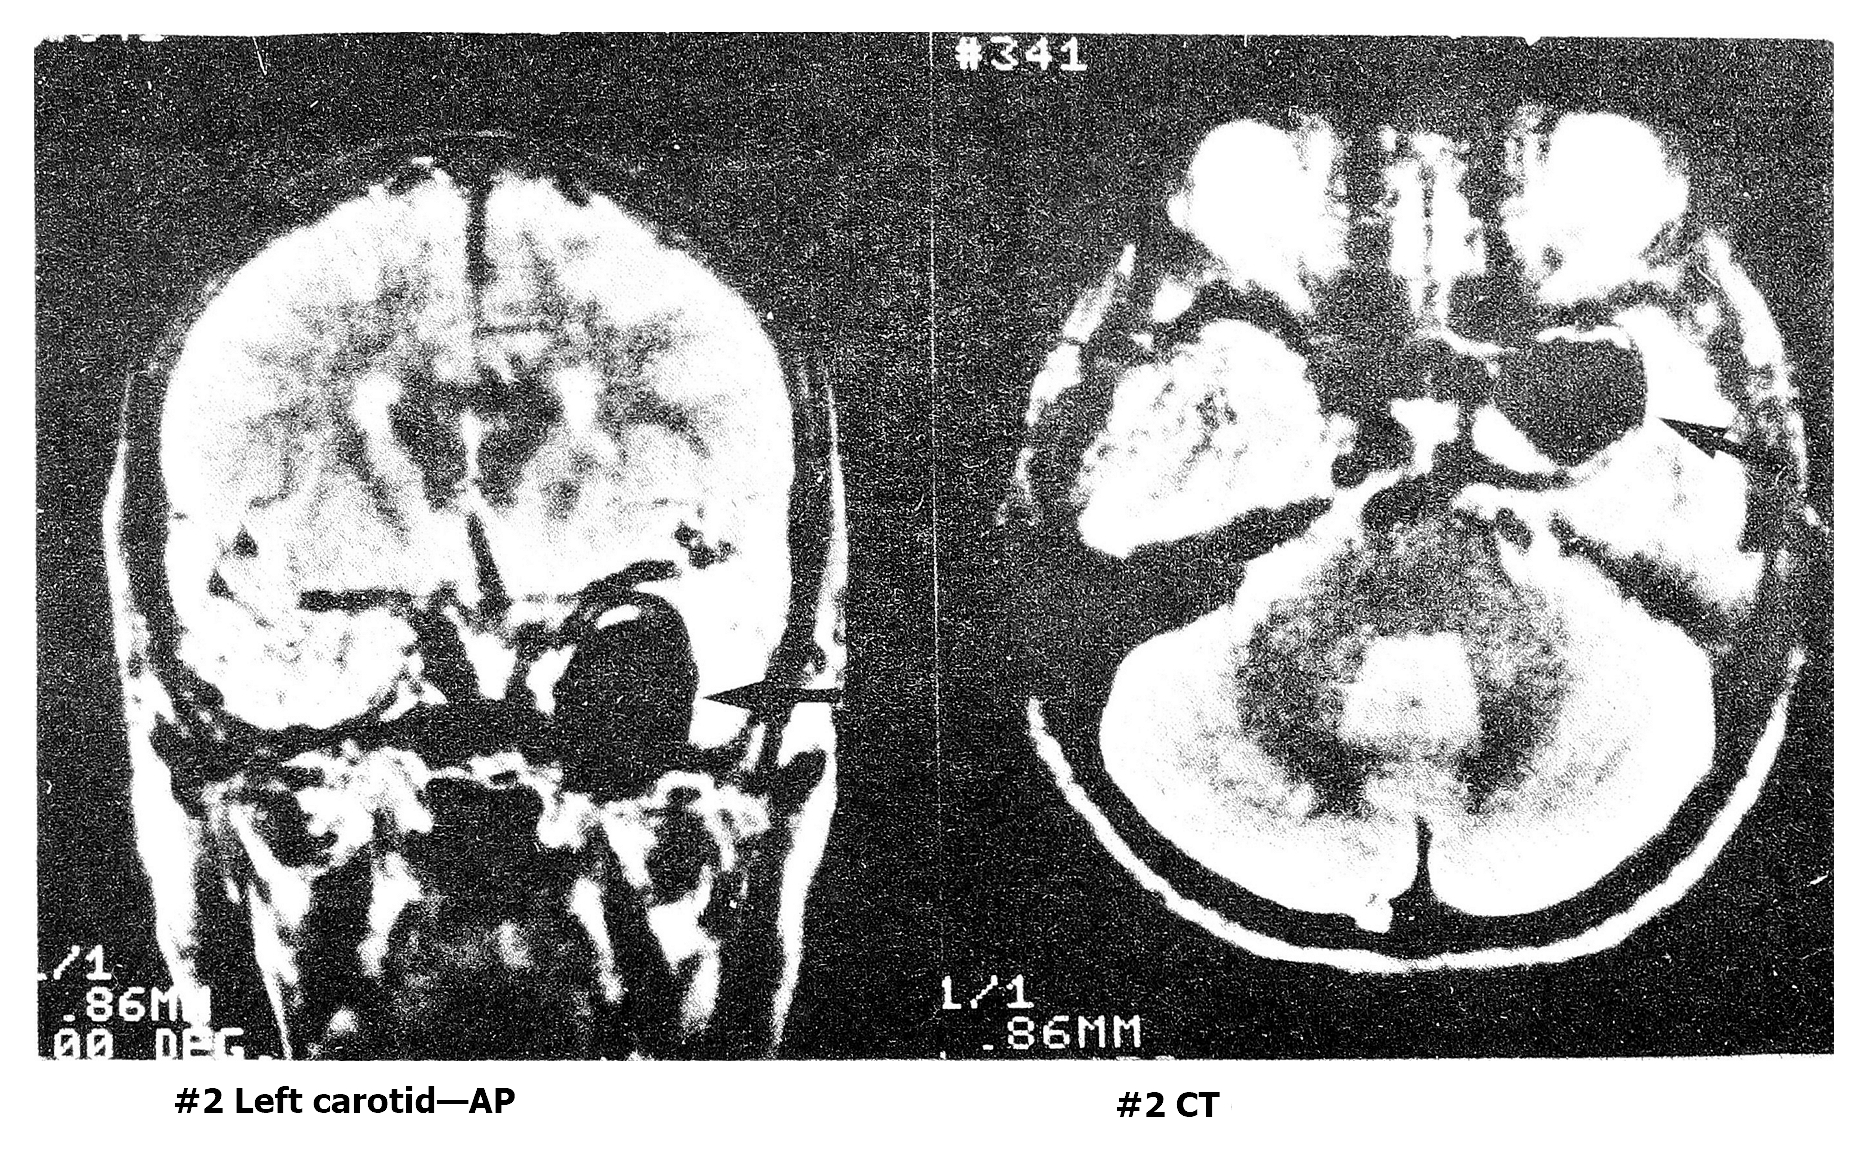

Рис. 2 А. Гигантская аневризма левой сонной артерии, по данным автографии и КТГ, до начала лечения (случай 2).

Рис. 2 Б. Тот же случай 9 лет спустя (по данным МРТ).